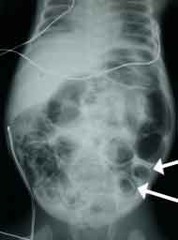

What is pneumatosis intestinalis?

Front

gas within intestinal wall that can be seen in patients with congenital variant or chronic steroids

What is necrotizing enterocolitis?

A condition in premature infants where the bowel undergoes necrosis and bacteria invade the intestinal wall -may be due to underdeveloped intestine or poor perfusion to the segment

Back

Symptoms of necrotizing enterocolitis

Vomiting Poor feeding Abdominal distention Stool retention Blood in stools Lethargy Decreased urine production